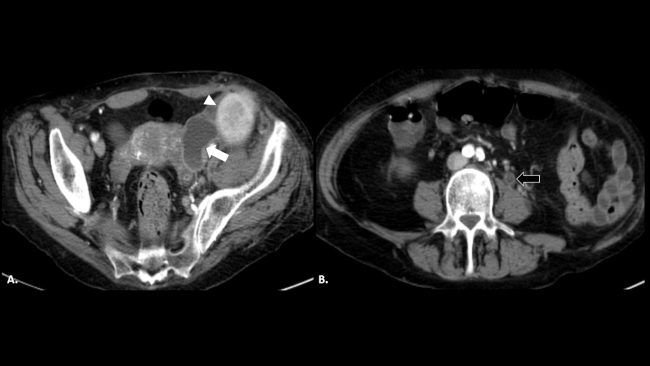

Tiempo atrás, la enfermedad ureteral era estudiada con radiología convencional por ureteropielografía ascendente, mientras que en la actualidad la ecografía, tomografía computada (TC) o resonancia magnética (RM) la han reemplazado y a pesar de no mostrar el reflujo ureteral de forma dinámica, evalúan de mejor manera sus complicaciones. Hoy en día, el diagnóstico tiende a ser más precoz, aun cuando la enfermedad no es inicialmente sospechada, debido al amplio uso de la TC para patología abdominal de guardia (►Fig. 1). Por lo tanto, conocer los hallazgos imagenológicos y las opciones terapéuticas contribuye al manejo de una enfermedad poco conocida.

Paciente con nefrectomía izquierda por infección del tracto urinario (ITU) y litiasis a repetición. TC de abdomen sin contraste en corte axial (a) donde se reconoce proceso inflamatorio retroperitoneal izquierdo, de difícil caracterización (flecha blanca). TC de abdomen con contraste endovenoso en corte axial (b) que muestra una estructura tubular dilatada retroperitoneal izquierda, con refuerzo de sus paredes y cambios inflamatorios regionales, compatible con empiema del muñón ureteral (flecha negra).

La TC con contraste endovenoso es por amplio margen la mejor técnica para el diagnóstico del EMU. Se trata de un estudio rápido, con alta sensibilidad y especificidad, que nos permite (►Fig. 2) no solo demostrar la existencia de un EMU visible como una estructura tubular dilatada en el trayecto del uréter remanente, con refuerzo y engrosamiento de su pared, sino que también nos ayuda a evaluar las posibles causas del mismo (litiasis, compresión extrínseca de la pared del muñón o tumores) y complicaciones como abscesos asociados en peritoneo o en músculo psoas (►Fig. 3).4,5,6,7,8

Reconstrucciones tomográficas en (a) coronal y (b) sagital del caso descripto en la ►Figura 1. Se reconoce la dilatación del uréter remanente con refuerzo de sus paredes a lo largo de todo su trayecto (flechas blancas).